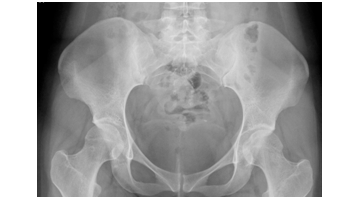

After a month without improvement, the orthopedics service is consulted again. At physical exam, the patient presented shortening of about 2cm of the right pelvic limb and limitation due to pain in the right hip mobility arches. A new antero posterior pelvic radiograph is requested, finding a right femoral trans-cervical continuity solution, without displacement, with varus angulation and cervical-diaphyseal angle of 117º (Figure 3).

Figure 3 14/10/2015 pelvic anteroposterior radiography one month after the initial date of admission. A right femoral transcervical continuity solution was observed, with no varus angulation and a cervical-diaphyseal angle of 17º.